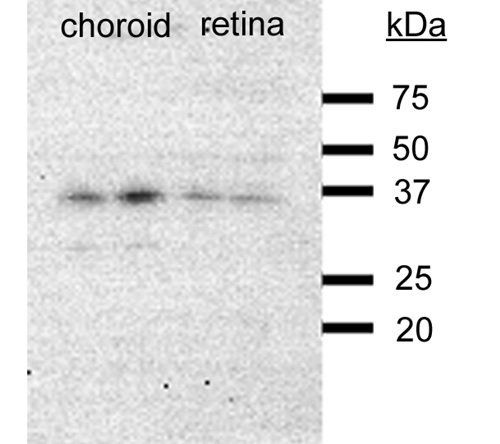

10 μg, 100 μg - Cubilin antibody [orb4997]Featured

ICC, IF, IHC-P, WB

Human, Mouse, Porcine, Rat

Rabbit

Polyclonal

Unconjugated